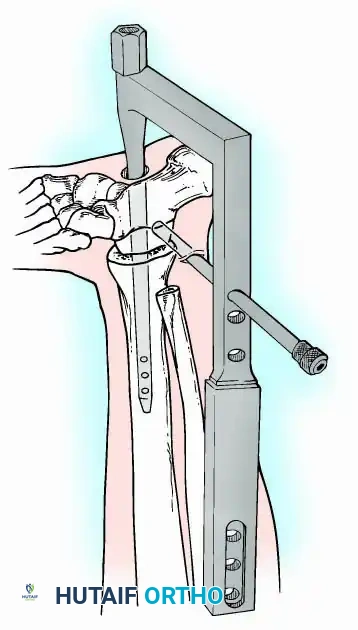

Modern iterations, such as the Calandruccio II compression device, offer greater latitude in pin placement to avoid compromised skin. Ring or circular external fixators (Ilizarov, Taylor Spatial Frame) are the gold standard for salvage situations, including active infection, massive bone loss, or failed TAA, as they allow for simultaneous compression, deformity correction, and early weight-bearing.

In cases of severe osteopenia or when extending the fusion to the subtalar joint (Tibiotalocalcaneal Arthrodesis), retrograde intramedullary nailing provides a load-sharing construct with superior bending stiffness.

For complex hindfoot reconstructions, specialized plating systems, including anterior or lateral locking plates, can be utilized to supplement screw fixation, particularly when structural allografts are required to restore limb length.